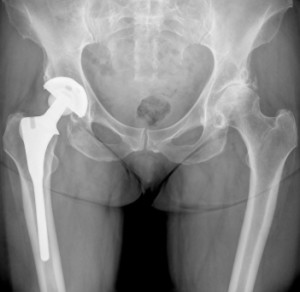

Hip replacement surgery removes a patient’s diseased or damaged natural hip joint and replaces it with artificial hip components that “articulate,” or fit, against one another. In total hip replacement procedures, the entire hip joint—including both the socket (acetabulum) and femoral head (the curved head at the top of the thighbone that fits into the socket)—is removed and replaced by synthetic components.

An alternate procedure is hip resurfacing, in which only the surfaces of the acetabulum and femoral head are revised; the “ball and cup” are made smoother and sheathed in a new synthetic surface, usually metal. Though many of the hundreds of thousands of Americans who have received artificial hip implants have reported increased mobility and a reduction in joint pain, others have had serious hip complications from poorly functioning devices. Hip replacement recalls have been issued for several implants, including the DePuy ASR hip, and the Stryker Rejuvenate model.